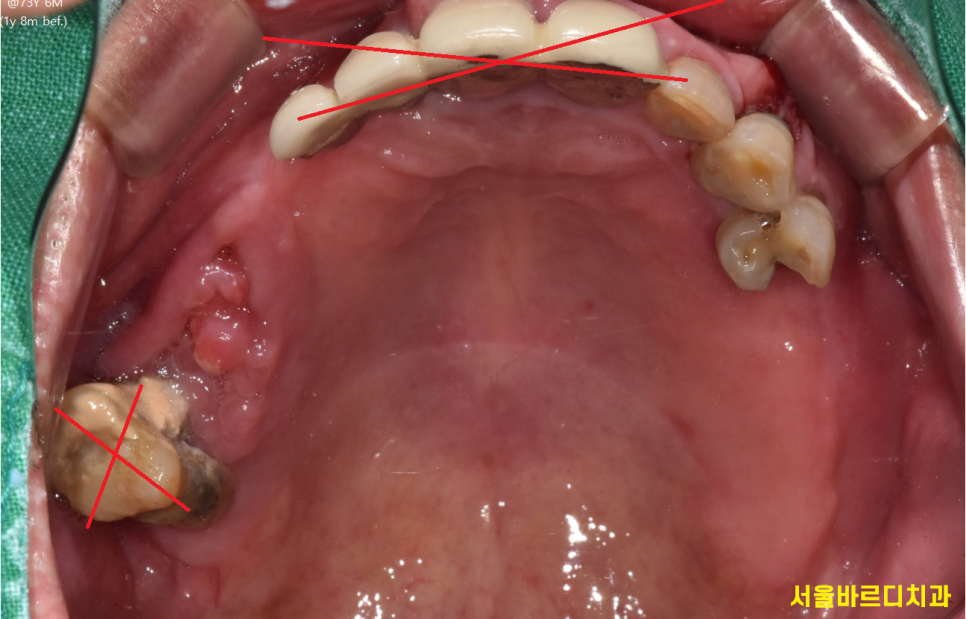

위에 치아부터 살펴보겠습니다.

230725

치아 뿌리가 다 드러날정도로 녹은 치아

염증으로 잇몸이 부푼 앞니는 발치가 필요했고

남은 3개 치아도 썩 좋진 않았지만...

최대한 관리하며

나중에 망가지면 발치하기로 하고...

이거라도 어떻게든 살려서

자연치아를 보존해야겠습니다.